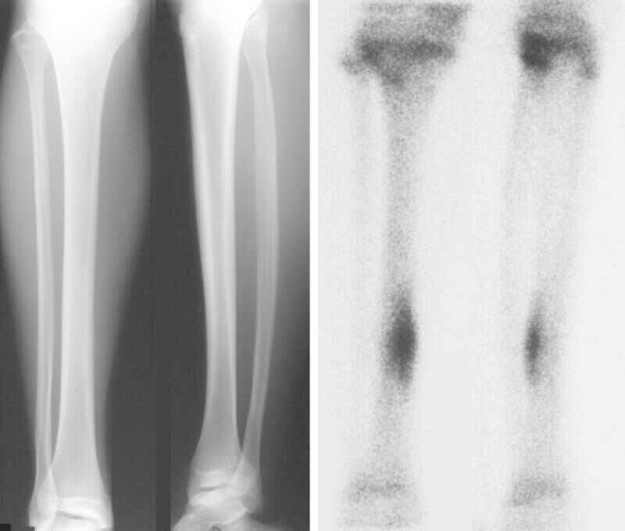

- Best – CT, MRI & Bone Scan